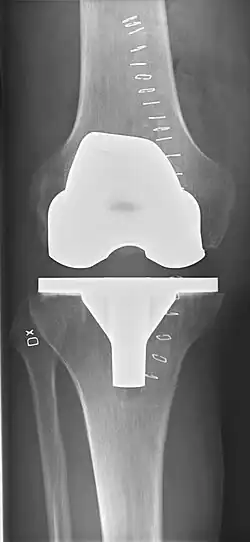

Knee replacement, also known as knee arthroplasty, is a surgical procedure to replace the weight-bearing surfaces of the knee joint to relieve pain and disability, most commonly offered when joint pain is not diminished by conservative sources.[1][2] It may also be performed for other knee diseases, such as rheumatoid arthritis. In patients with severe deformity from advanced rheumatoid arthritis, trauma, or long-standing osteoarthritis, the surgery may be more complicated and carry higher risk. Osteoporosis does not typically cause knee pain, deformity, or inflammation, and is not a reason to perform knee replacement.

Knee replacement surgery can be performed as a partial or a total knee replacement.[3] In general, the surgery consists of replacing the diseased or damaged joint surfaces of the knee with metal and plastic components shaped to allow continued motion of the knee.

The surgery involves exposure of the front of the knee, with detachment of part of the quadriceps muscle (vastus medialis) from the patella. The patella is displaced to one side of the joint, allowing exposure of the distal end of the femur and the proximal end of the tibia. The ends of these bones then are cut accurately to shape, using cutting guides oriented to the long axis of the bones. The cartilages and the anterior cruciate ligament are removed; the posterior cruciate ligament also may be removed but the tibial and fibular collateral ligaments are preserved.[20] Whether the posterior cruciate ligament is removed or preserved depends on the type of implant used, although there appears to be no clear difference in knee function or range of motion favoring either approach.[20] Metal components are then impacted onto the bone or fixed using polymethylmethacrylate (PMMA) cement. Alternative techniques exist that affix the implant without cement. These cement-less techniques may involve osseointegration, including porous metal prostheses. Finally, stability and range of motion are checked, followed by irrigation, hemostasis, placement of hemovacs, and closure.[21]

Femoral replacement

A round-ended implant is used for the femur, mimicking the natural shape of the joint. On the tibia the component is flat, although it sometimes has a stem that goes down inside the bone for further stability. A flattened or slightly dished high-density polyethylene surface is then inserted onto the tibial component so the weight is transferred metal to plastic, not metal to metal. During the operation any deformities must be corrected, and the ligaments balanced so the knee has a good range of movement, and is stable and aligned. In some cases the articular surface of the patella also is removed and replaced by a polyethylene button cemented to the posterior surface of the patella. In other cases, the patella is replaced unaltered.